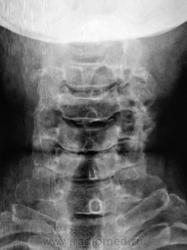

Анкилоз дугоотросчатых С2-С3 или как это назвать?

Скорее это не анкилоз, а вероятно связано с тем, что плоскость сустава не параллельна ходу R-луча( т.е мы не видим щель сустава).

Ну и анкилоз... Ну и что? Классика остеохондроза. Проблема больше в С4-С6. Тут должна быть клиника "плечо-рука". Клиника не указана.

Такая клиника наличествует

Киммерле случайно? Мне почему то видится.

Значит, окромя остеохондроза и Киммерли есть?

Думаю - ДА.